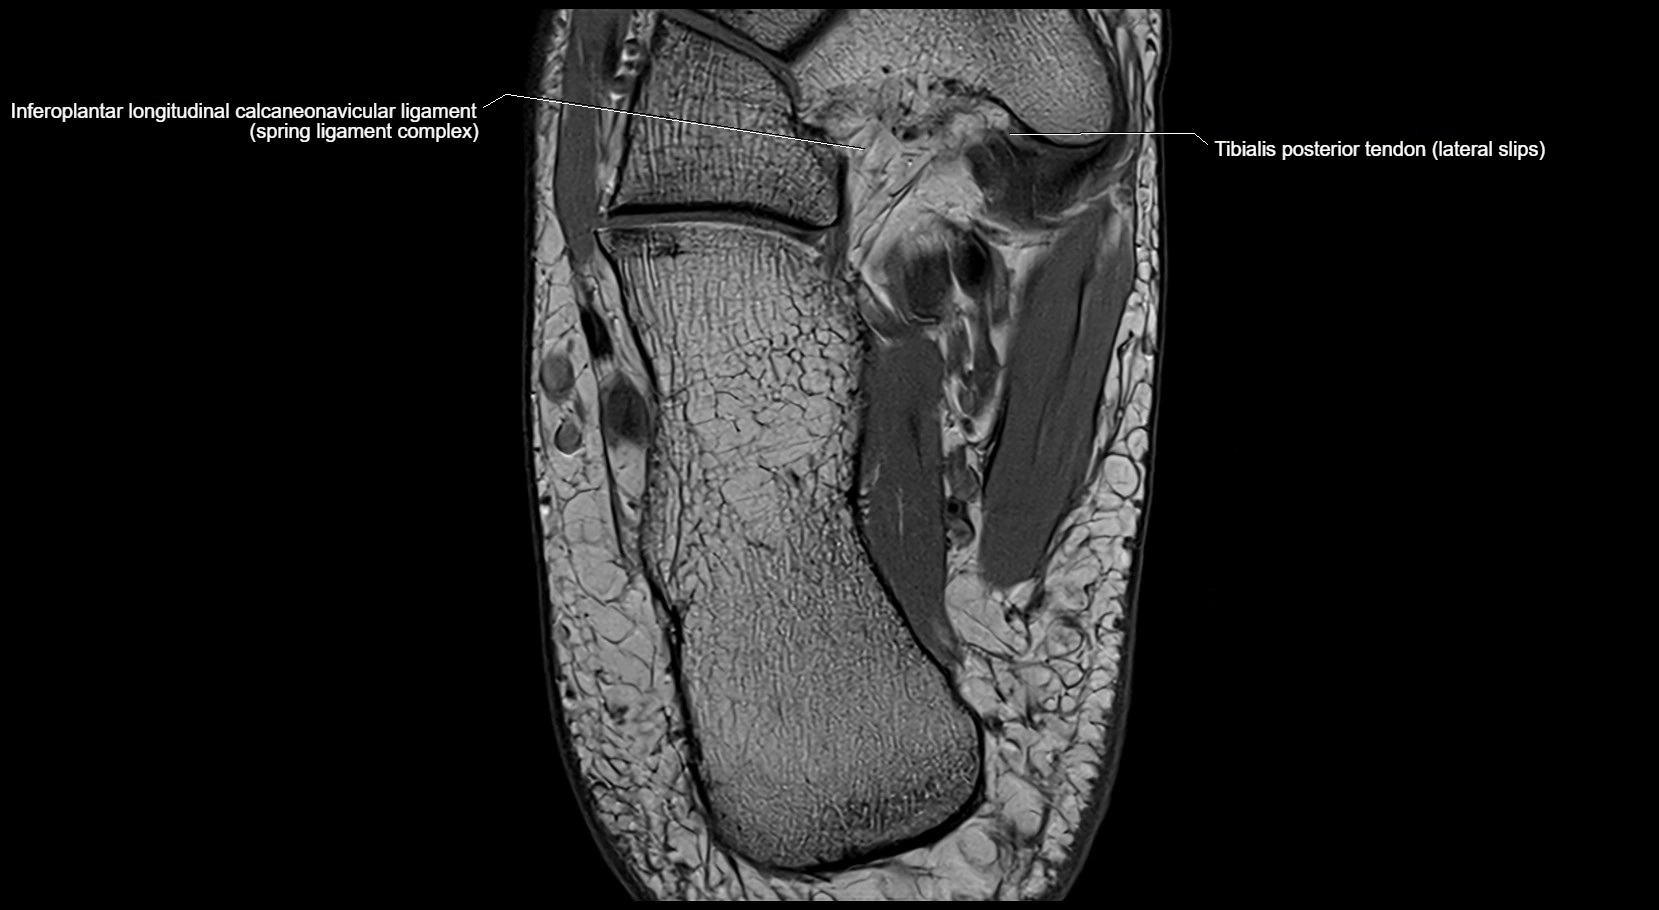

MRI image

image